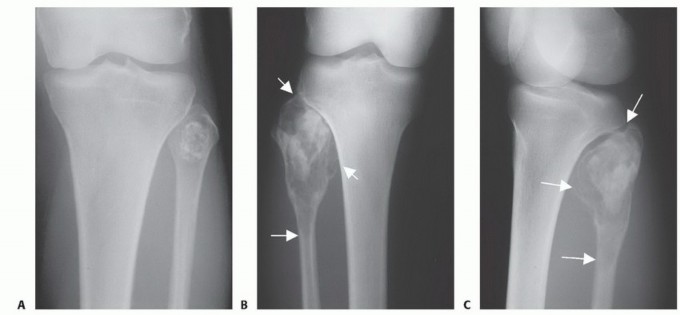

الأشعة السينية (X-rays): هي الخطوة الأولى غالبًا. توفر صورًا للعظم وتكشف عن التغيرات في بنية العظم، مثل التآكل، التصلب، أو وجود كتلة. يمكن أن تعطي مؤشرات أولية حول طبيعة الورم (حميد أو خبيث).

التصوير بالرنين المغناطيسي (MRI): يُعد MRI الأداة الأكثر قيمة لتقييم أورام العظام. يوفر صورًا مفصلة للأنسجة الرخوة المحيطة بالعظم (العضلات، الأوتار، الأعصاب، الأوعية الدموية)، ويحدد مدى انتشار الورم داخل العظم وإلى الأنسجة الرخوة المجاورة. وهو ضروري للتخطيط الجراحي للحفاظ على الطرف.

التصوير المقطعي المحوسب (CT Scan): يوفر صورًا تفصيلية لبنية العظم بدقة عالية، ويكشف عن تآكل القشرة العظمية، وتكوين العظم الجديد، وتكلسات الورم. كما يستخدم للكشف عن أي انتشار للورم إلى الرئتين (نقائل).